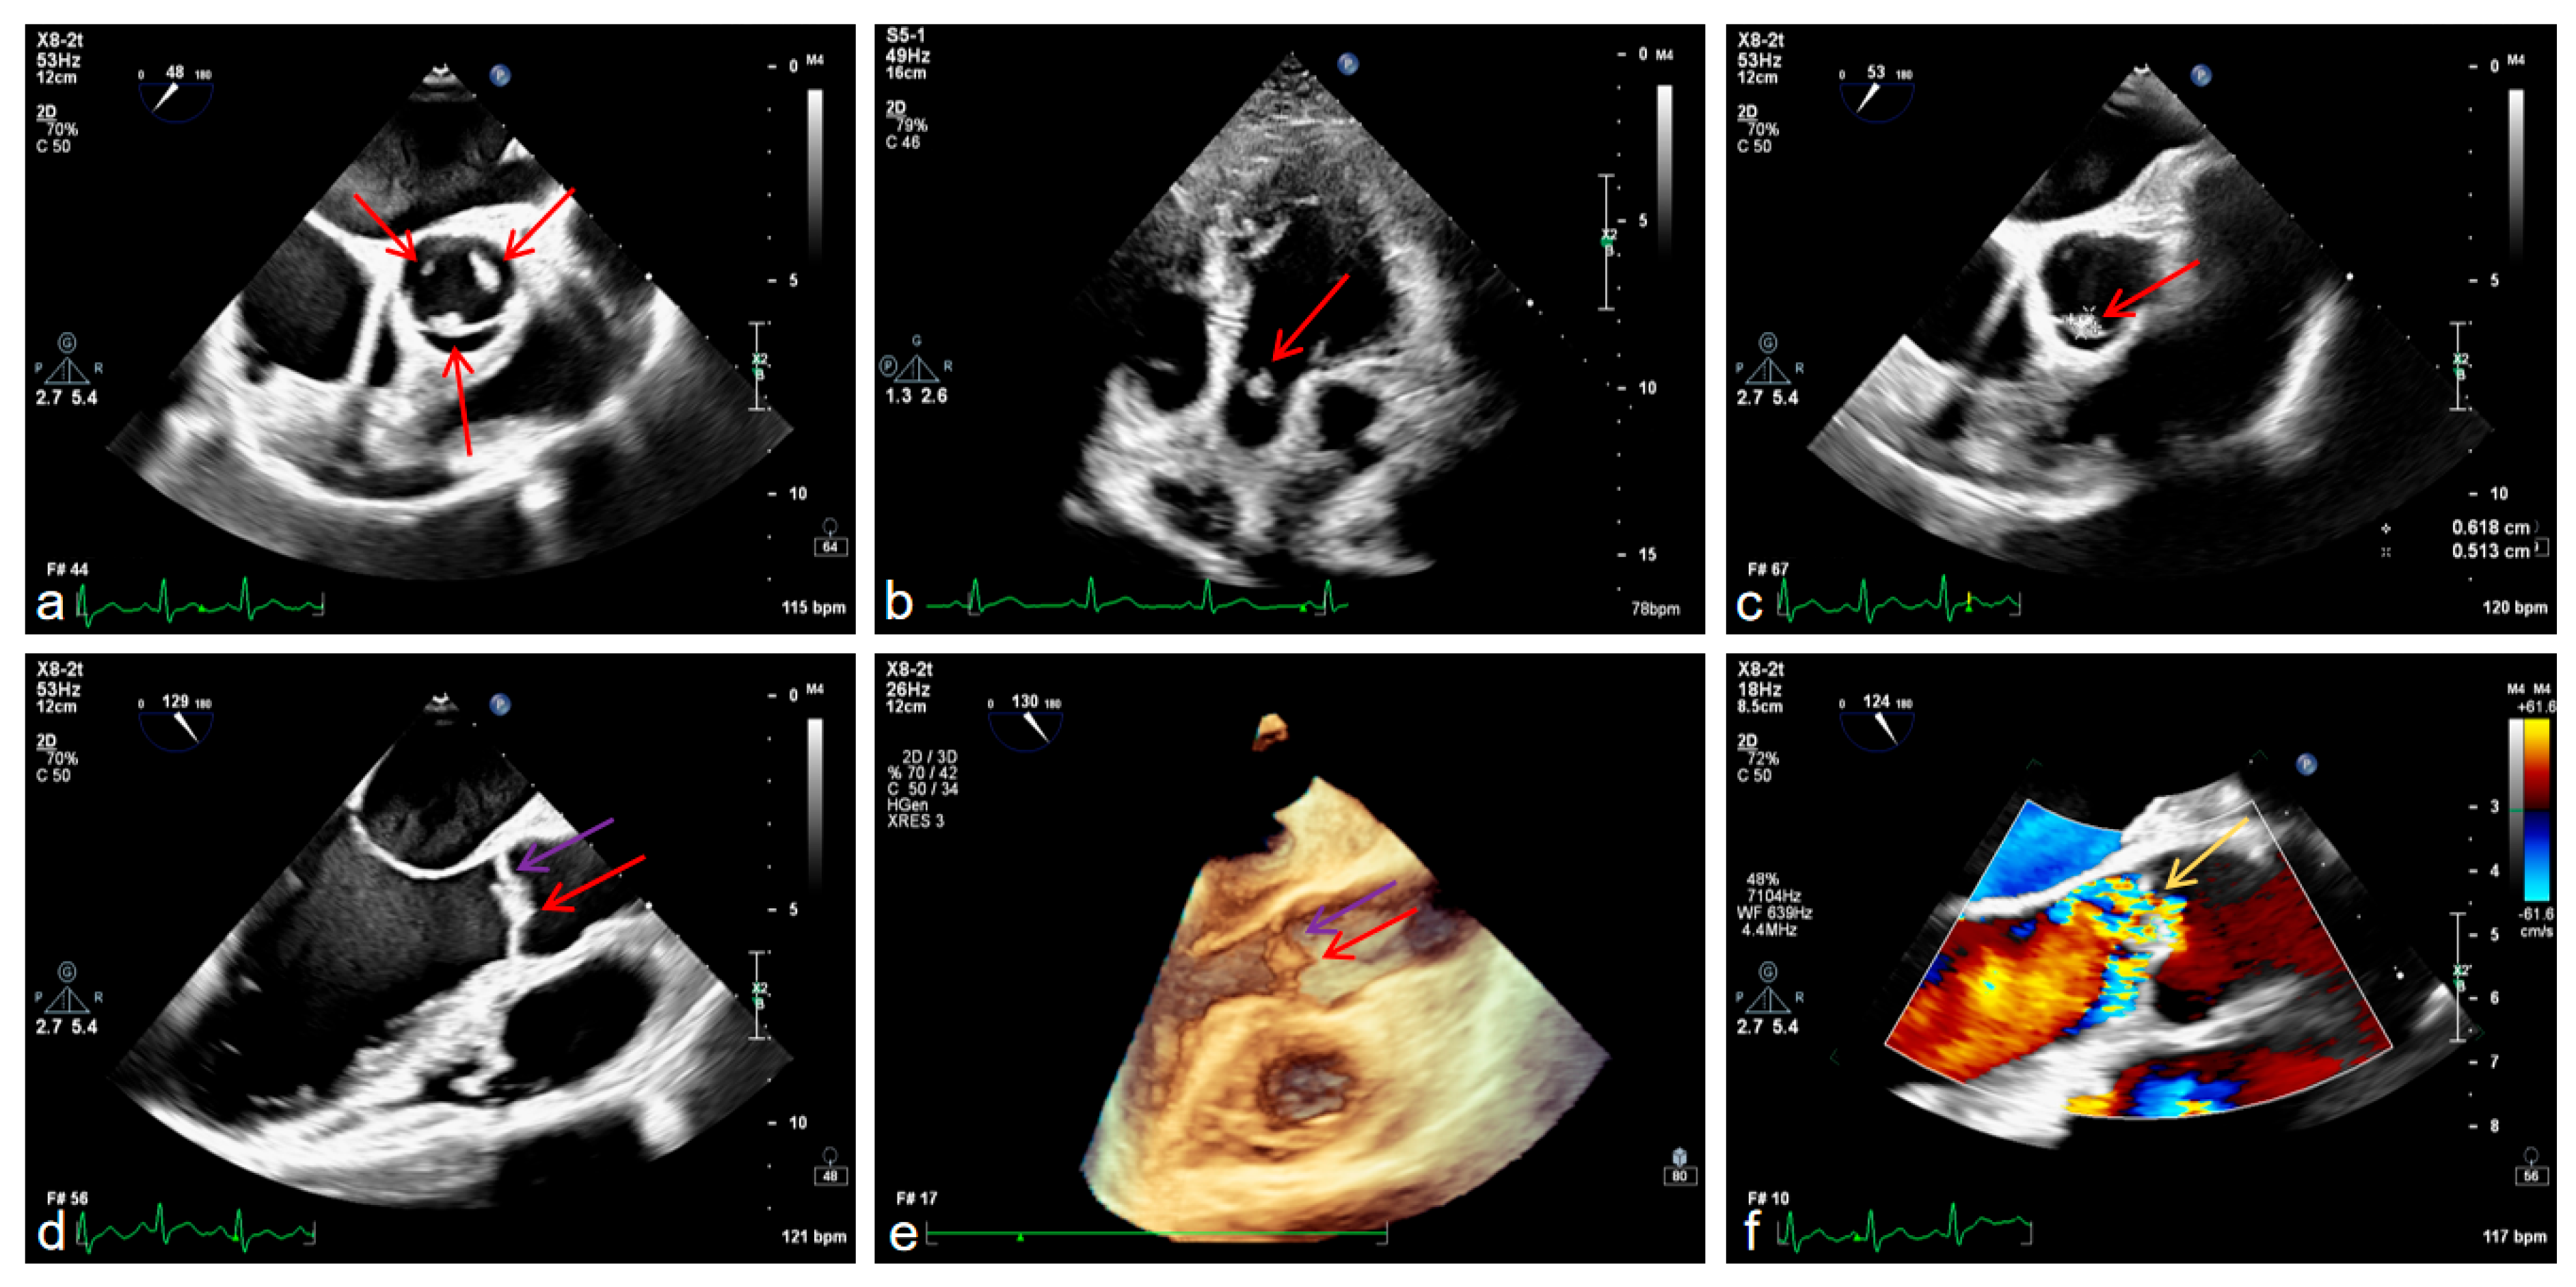

It is worth mentioning that we also conducted examinations related to the heart. Transesophageal echocardiography confirmed aortic valve prolapse with severe regurgitation and a vegetation attached to the valve leaflet, mild-to-moderate mitral regurgitation, left ventricular enlargement with ventricular wall thickening, and left atrial enlargement (Figure 4a–f).

Figure 4. Transesophageal echocardiography (TEE) findings, with red arrows indicating cardiac vegetations and purple arrows denoting aortic valve thickening (ad), 3D echocardiography also identifies cardiac vegetations and aortic valve thickening (e) and color Doppler echocardiography findings, with yellow arrows indicating blood shunting (f).